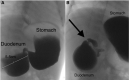

Duodenal stenosis is a rare congenital anomaly that is typically treated surgically, although endoscopic incisional therapy (EIT) and balloon dilation are minimally invasive alternatives. We present a case of a 15-month-old male with vomiting and difficulty tolerating solid food due to severe congenital duodenal stenosis. The patient underwent EIT and serial duodenal dilation to a diameter of 20 mm, which resulted in significant symptom improvement. Intralesional corticosteroid injection (ISI) was administered to help prevent the duodenal septum from restricturing. The combination of EIT, balloon dilation, and ISI was successful in treating the patient's congenital duodenal stenosis and avoided the need for surgery. However, further studies are required to confirm the efficacy of this treatment approach in this patient population. This report highlights the potential of this minimally invasive approach as an alternative to surgical intervention in the management of congenital duodenal stenosis.